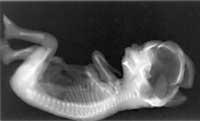

Ikerketan ere egongo da muga etikorik. Oro har eragozpenak izaten dira pertsonekin botikak probatzeko, eta are gehiago haur jaioberriak baldin badira. Zuen taldean surfaktante sintetikoak ikertzen dituzue. Nola egiten dituzue ikerketa horiek?Esperimentatu laborategiko animaliekin egiten dugu, ez haurrekin, noski. Haurrekin ezer probatu aurretik, animaliekin saiakera-piloa egiten dugu. Arruntena txerrikumeekin egitea da, baina Euskal Herrian askoz ere errazago lortzen dira ardiak. Beraz, ardiak ere ikerketarako egokiak direnez, arkumeekin egiten dugu lan. Haurdun diren ardiak hartu eta zesarea egiten diegu garaia baino lehen; arkumearen birikek surfaktanteen aurrean nola erantzuten duten aztertzen dugu horrela. Surfaktante sintetikoekin ere birikak azkar heltzeko gai diren ikusten dugu.

Fetuaren nerbioak eta muskuluak lanean hasten dira, haien arteko konexioak garatzen ari baitira. Organo garatu berriak probatzen ere hasten da fetua: inguruko likido pixka bat edan eta giltzurrunek prozesatzen dute. Fetua 8 cm luze da, eta buruak gorputzaren luzeraren erdia hartzen du oraino.

Eskeletoaren osifikazioa gero eta abiada biziagoan gertatzen da. Fetua burua, besoak, hankak eta ezpainak mugitzen hasten da.

Fetuaren oinarrizko hainbat organo gai dira funtzionatzen hasteko, baina ez nerbio-sistema zentrala eta arnas-aparatua. Izan ere, oraintsu hasi dira birikak surfaktantea sortzen: albeoloak zabaldu eta birikak arnasten hasteko prestatuko ditu.

Birikak arnasteko gai dira eta nerbio-sistema zentrala nahikoa heldu da: dagoeneko arnas-mugimendu erritmikoak zuzentzeko gai da eta gorputz barneko tenperatura erregula dezake.